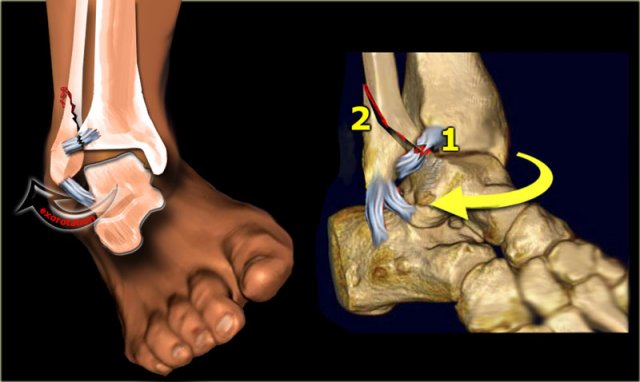

Weber C in detail

Stage 1

Weber C is seen in approximately 20% of ankle fractures.

It is the most difficult fracture to diagnose and the Lauge-Hansen system will help you to understand the fracture-mechanism, as this will be an enormous help.

According to Lauge-Hansen the fracture results from an exorotation force on the pronated foot.

Stage 1 The first injury will occur on the medial side, which is under maximum tension due to the pronation.

It will lead to rupture of the medial collateral ligament or avulsion of the medial malleolus.

Now the injury can stop and there will only be a rupture of the medial collateral ligaments or avulsion of the medial malleolus.

Lauge Hansen calls this PE stage 1.

We can not cathegorize this in the Weber classification, since there is no fibular fracture.

In many cases the injury progresses to a higher stage.

Stage 2-3

The talus rotates externally and moves laterally because it is free from its medial attachment.

Due to the pronation, the lateral ligaments are not under tension and the fibula can move away from the tibia.

This causes rupture of the anterior syndesmosis. This is stage 2.

Continuous force will twist the fibula and displace it distally, while proximally it is fixed to the tibia.

Finally the interosseus membrane will rupture up to the point where the fibular shaft fractures. This is stage 3.

This is always above the level of the syndesmosis.

In many cases it is visible on the radiographs of the ankle, but in some cases the fracture is located high and will only be visible on a radiograph of the lower leg.

This last type of fracture is also called Maisonneuve fracture.

Here we see the different stages in the axial plane.

1. Medial avulsion fracture or rupture of the collateral band

2. Rupture of the anterior syndesmosis

3. Suprasyndesmotic rupture of the fibula due to rotation

4. Posterior malleolus fracture or rupture of the posterior syndesmosis

Scroll through the images.